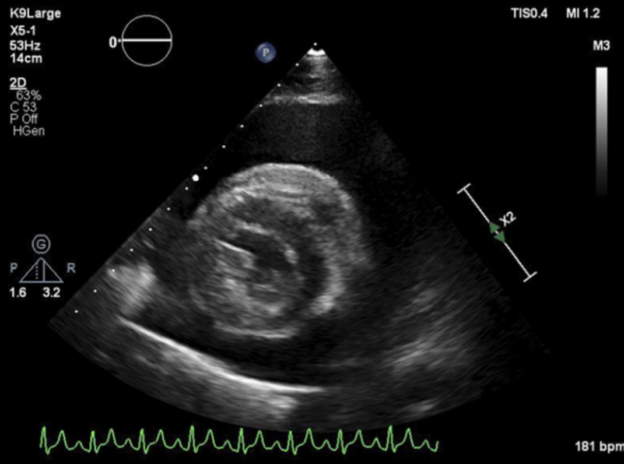

This lesson will focus on TFAST® Fundamental Echocardiography including image acquisition of the TFAST® Echo Views in the standing position. We will teach the fundamental right-sided and left-sided echo views and how to use them for patient assessment for dogs with chronic valvular disease, dilated cardiomyopathy and pulmonary hypertension and hypertrophic cardiomyopathy in cats. We will also discuss applying the EPIC guidelines from the Cardiac Education Group for management of early chronic valvular disease dogs with pimobendan. We will also discuss imaging the caudal vena cava and lung as fallback views to assess for right sided and left sided heart failure respectively.

2. Interpret information gained from TFAST® fundamental echocardiography to assess for chronic valvular disease, DCM, pulmonary hypertension and HCM in cats.